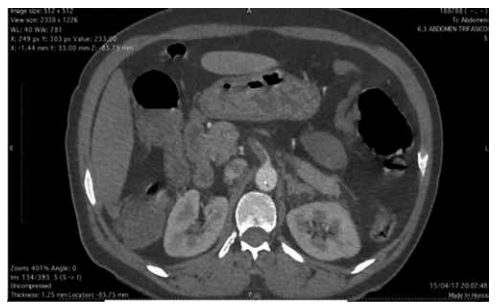

Mulher de 78 anos, hipertensa e fibrilação atrial crônica, sem anticoagulação, apresenta dor abdominal difusa de início súbito há 4 horas, desproporcional ao exame físico. FC: 118 bpm, PA: 132/74 mmHg, afebril. Abdome flácido, sem sinais de peritonite. Leucograma: 18.500/mm³, D-dímero: elevado, Lactato: 4,5 mmol/L. TC de abdome com contraste demonstrada na imagem a seguir:

(Arquivo pessoal; imagem usada com autorização)

Qual é a melhor conduta inicial?